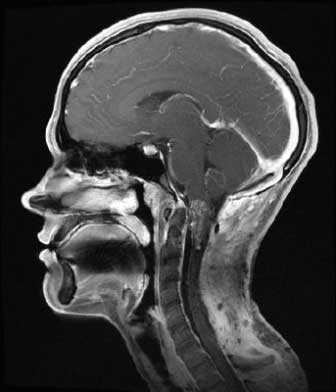

- МРТ – этот метод обладает высокой точностью, достигающей 99%. МРТ позволяет оценить изменения в паутинной оболочке, определить местоположение кисты и исключить другие заболевания с похожими симптомами, такие как опухоли и абсцессы.

Как МРТ покажет арахноидит головного мозга?

Слипчивый арахноидит характеризуется слипанием нервных корешков и спинного мозга, которые могут выглядеть как слипшиеся пучки на МРТ-снимках. Этот признак лучше всего виден на Т2-взвешенных изображениях. Повышенный сигнал от окружающих тканей на Т2-взвешенных изображениях указывает на отек и воспаление.